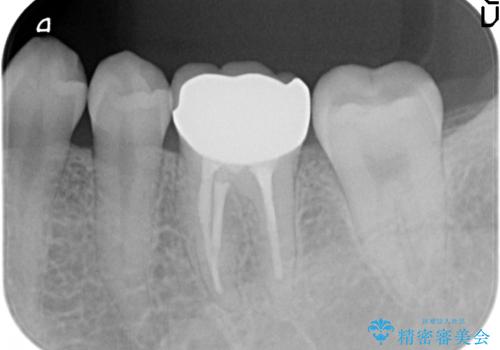

- 他院にて左下6番目の歯の根管治療を行っていたが、痛みが引かず抜歯を提案されたため、何とか歯を残せないかと当院にいらっしゃった方の症例です。

顕微鏡下で精密根管治療を行い、症状の緩解を確認後、オールセラミッククラウンによる補綴を行いました。

今回用いたオールセラミッククラウンはジルコニアフレームという白い素材の上にセラミックを盛っているため、審美性が非常に高いのが特徴です。

また、ジルコニアは人工ダイヤモンドの材料にも使われているほど高い強度を持っており、そのためオールセラミッククラウンは審美性だけでなく、奥歯やブリッジの補綴も可能とするクラウンです。